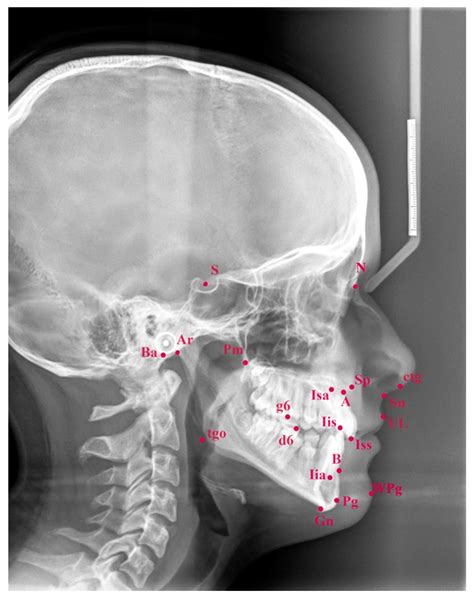

Interpreting a Cephalometric X Ray requires a thorough understanding of craniofacial anatomy and orthodontic principles. The orthodontist analyzes various landmarks and measurements to assess the patient’s dental and skeletal relationships. Some of the key landmarks and measurements include:

Key Landmarks

The following table outlines some of the key landmarks used in Cephalometric X Ray analysis:

Landmark Description

Sella (S) The center of the sella turcica, a depression in the sphenoid bone

Nasion (N) The most anterior point of the frontal bone at the nasofrontal suture

Orbitale (Or) The lowest point on the inferior margin of the orbit

Pogonion (Pog) The most anterior point on the chin

Gnathion (Gn) The most inferior point on the symphysis menti